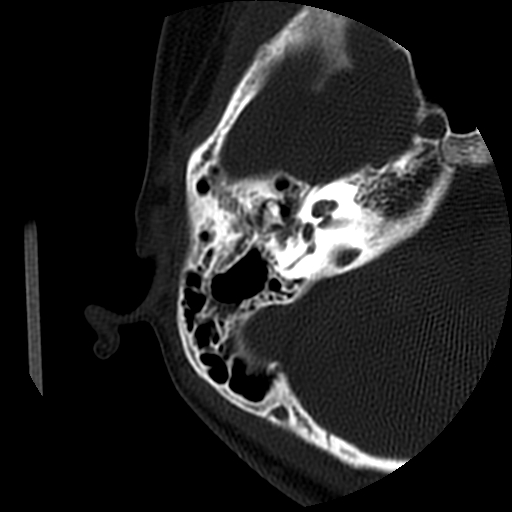

以下是引用随光逐影在2009-8-19 7:25:00的发言:[br]右侧慢性中耳乳突炎,右侧中耳腔及外耳道肉芽肿或胆脂瘤形成。